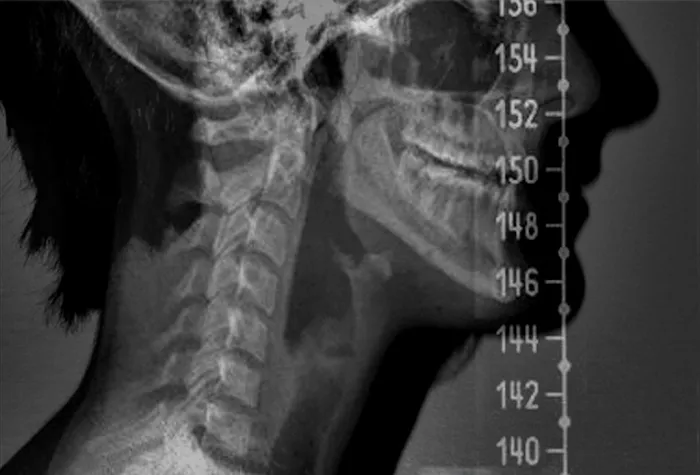

Jun 24, 2025 · Kathy MundellI love this place! Dr. May was very thorough with my exam, he explained my treatment plan while we were reviewing my x-rays. He gets you in and out of there at your scheduled time. I love that he is considerate of our time. I had been to physical therapy and an ortho doctor with no results. Finally, I am getting some relief.